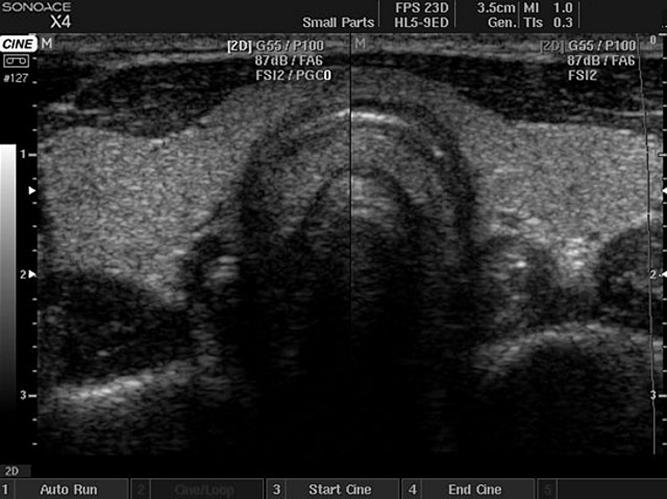

- трансабдоминальное ультразвуковое исследование органов малого таза и трансректальное УЗ-исследование простаты;

- Трансректальное УЗИ позволяет детально изучить структуру предстательной железы, ее размеры и выявить патологию еще на ранних стадиях.

- С помощью УЗИ оценивается состояние предстательной железы, почек и мочевого пузыря.